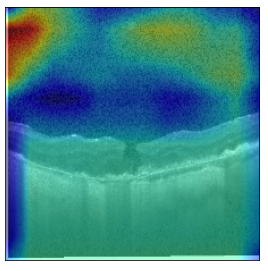

Original Image

Explanation B

Explanation C

Explanation D

GradCAM

Fig 6, 7, 8 and 9 depicts the visualization of correct predictions by our proposed CNN model where fig 6 is class CNV, fig 8 is class DME, fig 7 is DRUSEN and finally, fig 9 is NORMAL. Here the first photo in every class is the original image. The LIME map of our suggested model’s prediction is shown in image B whereas in image C the positive region is highlighted in specific sections on the original image. For Image D we have increased the number of features from 5 to 10 thus more regions have been predicted as the positive region which is highlighted in green. After increasing the features from 5 to 10, some of the regions are predicted wrongly. The red regions represent the output of incorrect prediction. The following image represents the Grad-CAM heatmap highlighting the regions with our model’s prediction.